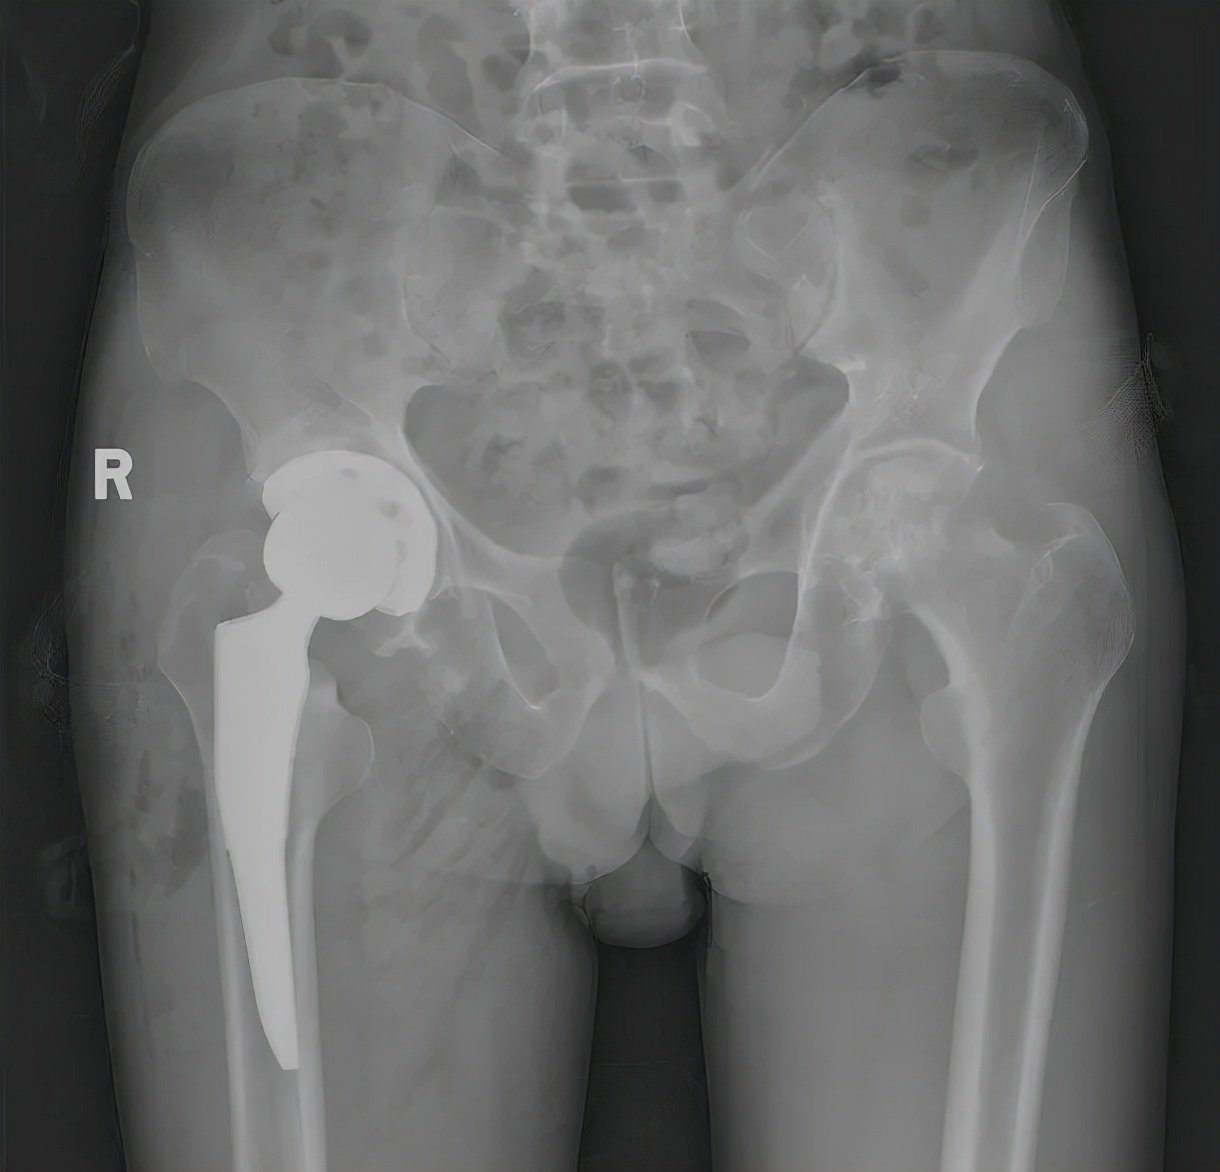

给予查阅X线片后,发现曾某髋关节磨损破坏严重,如下图1所示,股骨头严重变形,髋臼磨损上移并变大,同时伴有髋臼严重的骨质增生。阅片后,建议曾某行人工关节置换术。曾某提出了一系列问题:

曾某在获得答疑后,欣然要求手术 。但曾某的髋关节病变严重,如图1。术前不进行严密规划,术中很可能出现磨穿髋臼、髋臼上移、试膜不配套和反复找寻匹配假体的窘迫和困难,从而导致手术不理想。为此,董伊隆特地予以进行术前建模。何为术前建模?就是利用影像学数据,术前进行模拟手术,进行假体型号的大小、角度的确定,从而为术中手术提高准确指导,如图2。

图1曾某股骨头严重变形,髋臼磨损上移并变大,同时伴有髋臼严重的骨质增生。

手术中,曾某的髋臼磨损、股骨头坏死和骨质增生都如术前预料的一样严重。而术中实际手术所确定的假体型号和角度也与术前模拟手术一致,从而减少了手术时间,避免了并发症的发生。术后第二天曾某便下地负重行走,发出如此感慨“跛行数十载,一朝换新生”。

图3 曾某股骨头严重变形,髋臼磨损上移并变大,同时伴有髋臼严重的骨质增生。